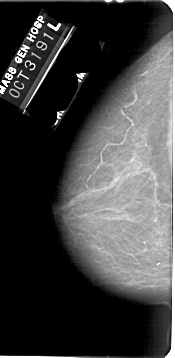

A_1737_1.LEFT_MLO

LEFT_MLO LINES 5491 PIXELS_PER_LINE 2776 BITS_PER_PIXEL 12 RESOLUTION 43.5 NON_OVERLAY